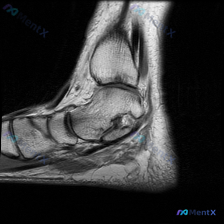

刚整理完这例踝关节MRI读片资料,分享一下完整的分析思路,这个病例的影像特征其实挺典型的,一起看看。 病例影像基础信息 这是一张踝关节MRI T1加权序列的正中矢状位图像,图像质量清晰,结构对比度好,无明显运动伪影,可以清晰辨认胫骨远端、距骨、跟骨、舟骨等骨性结构。 核心阳性发现 1. 骨信号异常:...